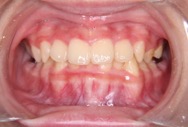

症例

矯正歯科専門の歯科医師が専門的な知識と確かな実績を

もとに患者様にあった最適な治療プランをご提案します。